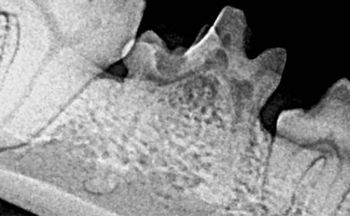

Attention to persistent primary teeth is essential to the dental health of our patients, especially smaller breeds such as Maltese, Yorkshire terriers, Pomeranians and miniature Schnauzers.